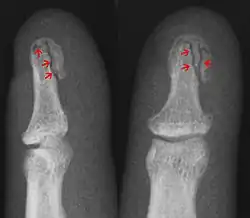

• Avulsion fracture – a fracture where a fragment of bone is separated from the main mass

In the fingertip. More images

Avulsion fracture A fragment of bone is separated from the main mass (image shows a Busch fracture)